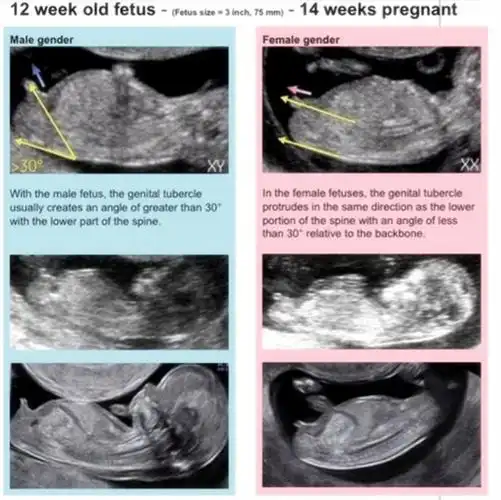

"nub"实际上就是指胎儿的"生殖节",一般在胎儿11-13周的时候,生殖器官